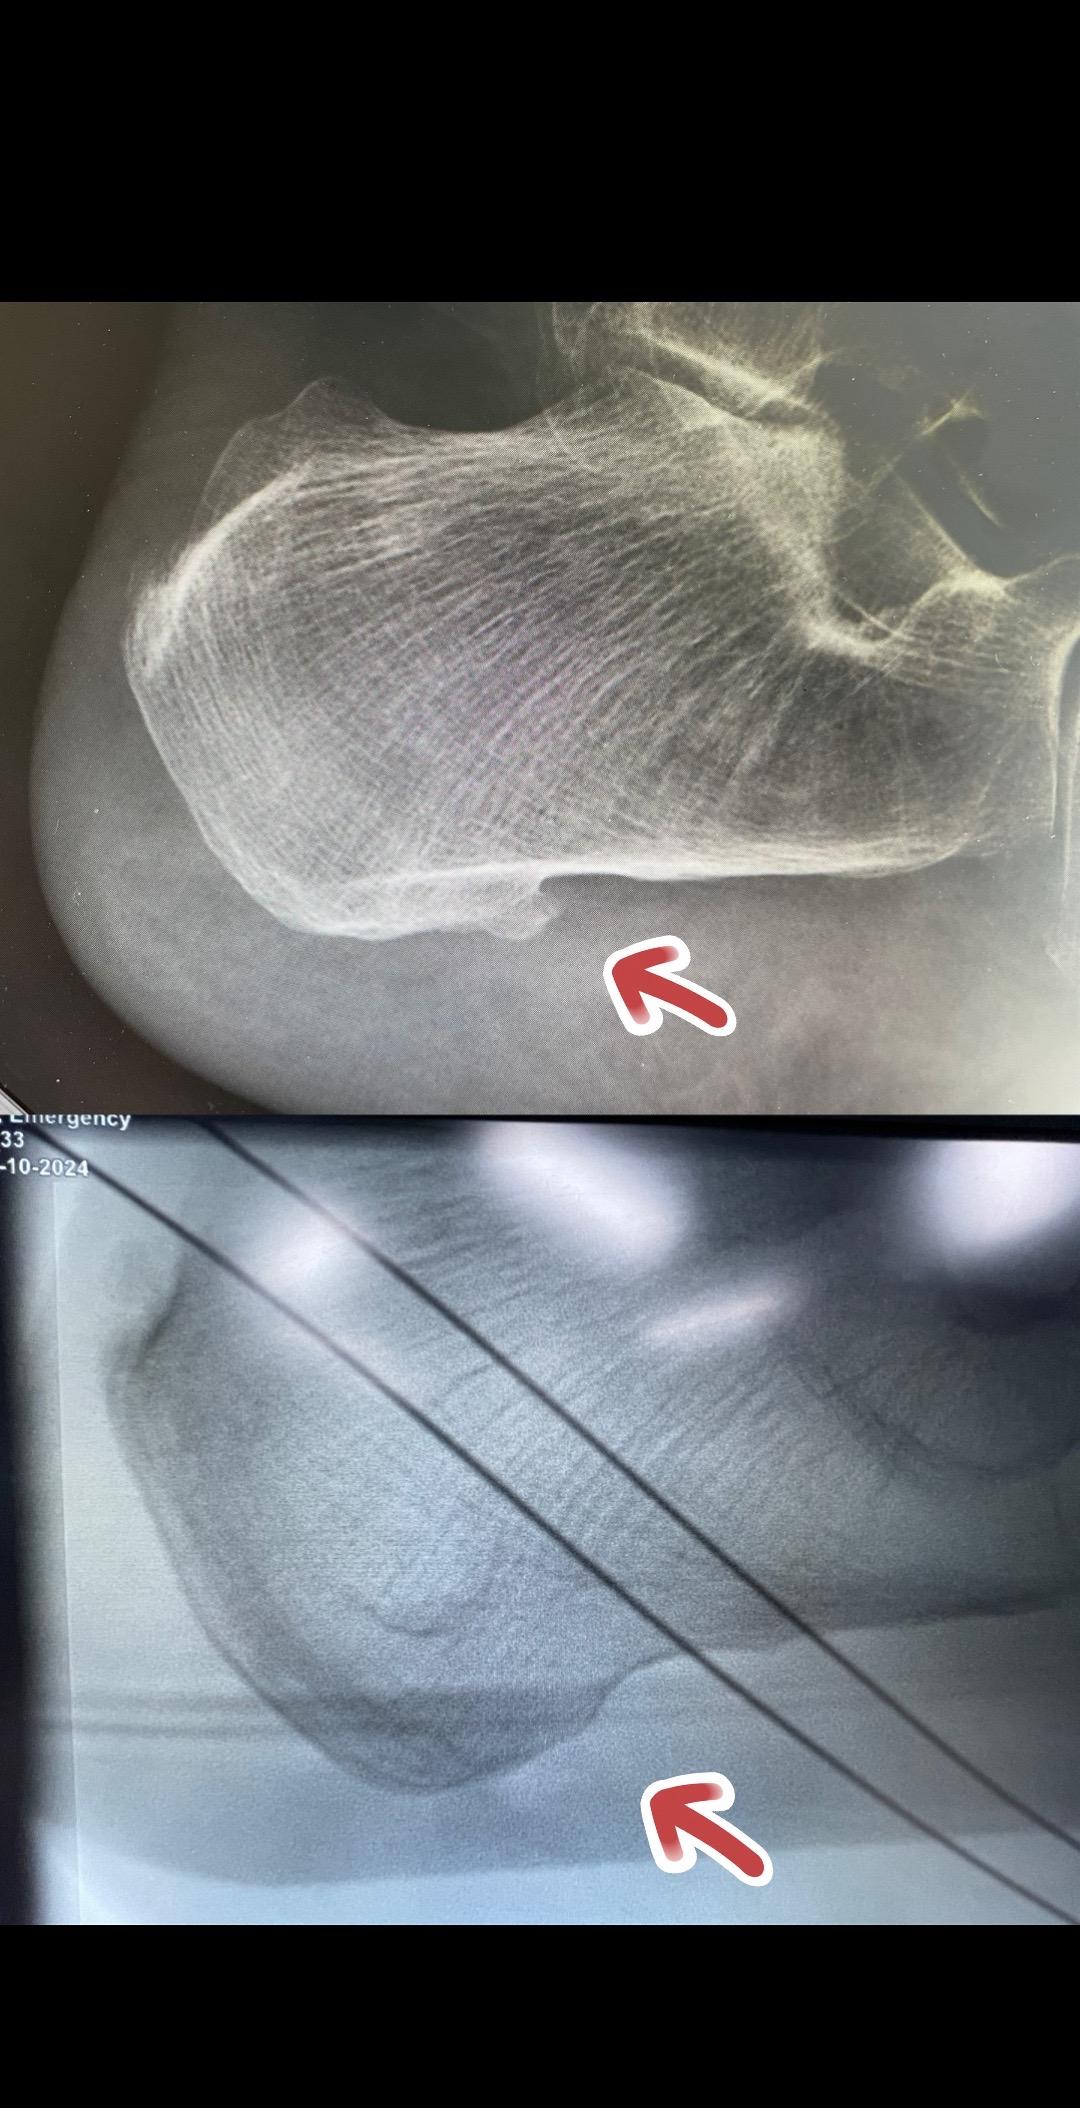

顽固性跟痛症,关节镜下治疗。

看骨科的叶培